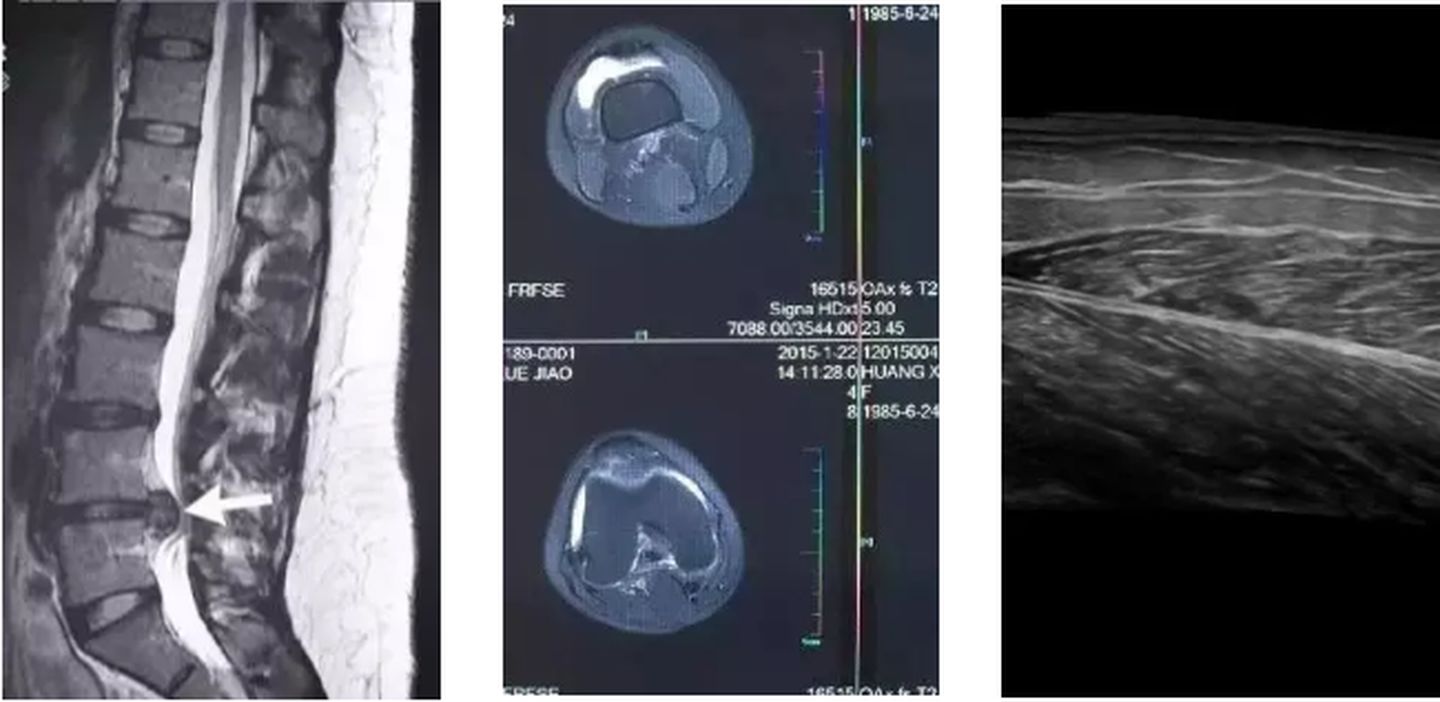

▲ 这是核磁共振对比影像

▲ 这是CT断层扫描影像

▲ 这是超声扫描影像